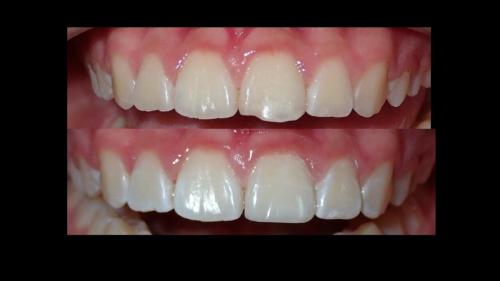

large-Resultados sin que se note ortodoncia

large-Resultados con balance

large-Ortodoncia Lingual

large-Resultado de avance de la mandibula

large-Ortodoncia lingual invisible

large-Lingual

large-Fractura con resina

large-Fractura

large-Combinacion con cirugia

large-Diapositiva14

large-Cambios en el perfil

large-Cambio magico

large-Cambio labial

large-Cambio en el perfil

large-Adultos -Se puede

large-Avance de mordida

large-Sonrisa en adulto

large-Sonrisa Adulto